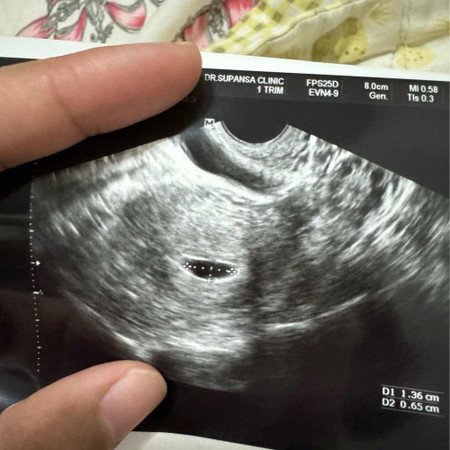

เราพึ่งท้องเเรก น่าจะได้ประมาณ6วีค ไปอัลตร้าซาว์ครั้งเเรก ไม่เจอตัวน้อง เจอแต่ถุงตั้งครรภ์ หมอนัดซาว์อีกทีวันที่2นี้ รู้สึกกังวลมากค่ะ แม่ๆเจอน้องตอนกี่wกันบ้างค่ะ

อดใจรอไม่ไหววันนี้ไปซาว์เจอตัวน้องพร้อมเสียงหัวใจเเล้วค่ะทุกคน ❤️